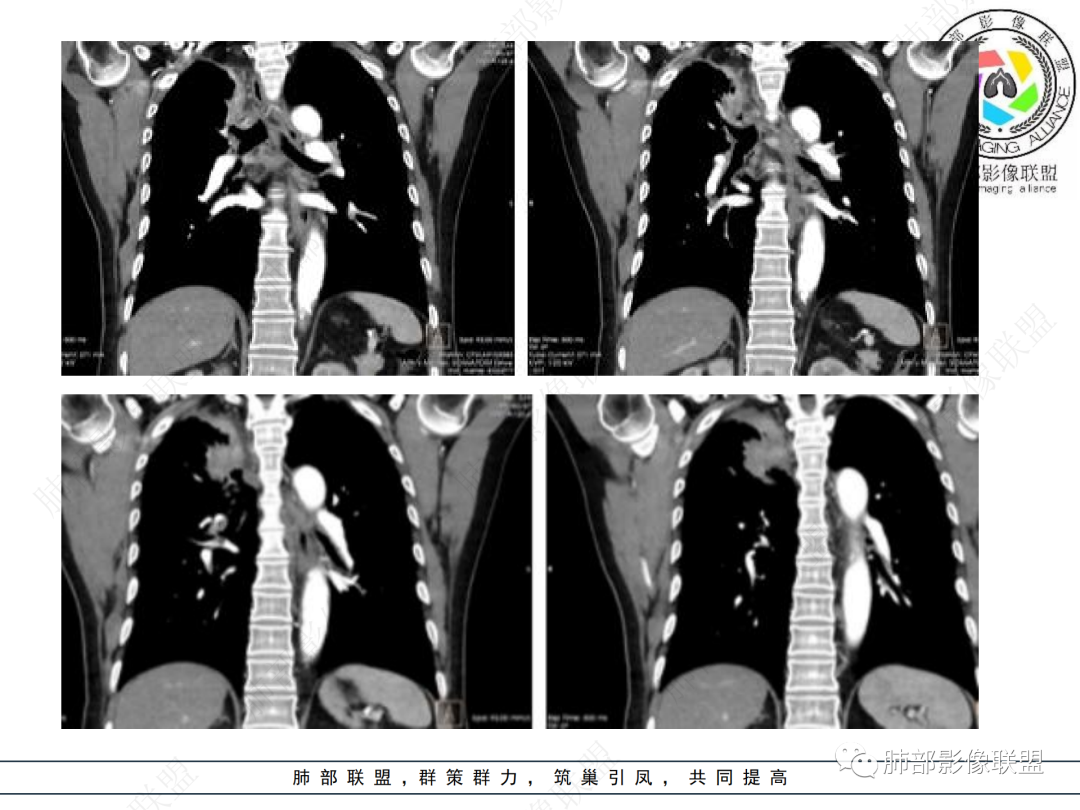

病史2年。右肺上叶团片影,边缘部分清晰,平直,相邻纵隔侧胸膜黏连较广泛,周围见斑点。增强均匀强化。首选炎性肉芽肿性病变(慢性炎症,结核)。肿瘤性病变待排。食道上段形态异常建议相关检查。

右上胸廓缩小,叶间裂移位,尖段软组织影,前段支气管壁增厚,双上肺多发结节及条片影,增强后尖段软组织影内见多发低密度影,呈环状强化,考虑慢性肉芽肿,腺癌待排

右肺上叶体积变小,见不规则实性病灶,边缘有平直,长软毛刺,邻近胸膜明显增厚,叶间胸膜牵拉上提、局部凹陷;病灶周围不干净,可见长索条影;近端支气管壁略增厚。增强后增强不均匀,有低密度坏死,间隔较厚。考虑慢性炎性肉芽肿,结核可能,鉴别腺癌。

右肺上叶尖后段不规则斑块病灶,后缘以斜裂为界,有边缘平直,周围见纤维及多发小卫星灶,邻近胸膜反应性增厚,纵隔胸膜下少量积液,同时右肺中叶内侧段支气管扭曲及牵引性扩张,周边见爬行征,胸廊入口变窄,纵隔未见淋巴结肿大,综合上述慢性炎性肉芽肿,结核可能性大,支气管镜肺泡灌洗!

结合本病例,老年男性患者,慢性病程,急性加重,无吸烟史,影像学表现为右肺上叶尖后段斑片实变密度影,整体边界清晰,边缘平直收缩为主,周边散在纤维条索影,内部见支气管内粘液栓,血管影走形正常,没有明显破坏,增强扫描明显强化,缺乏典型分叶毛刺、胸膜改变,病灶也未显示清楚的磨玻璃勾边,病灶大而肺门纵隔未见肿大淋巴结,综合考虑慢性炎性肉芽肿可能性大。但恶性,结核能完全排除吗?我想对临床医生来说还是有很大考验的。